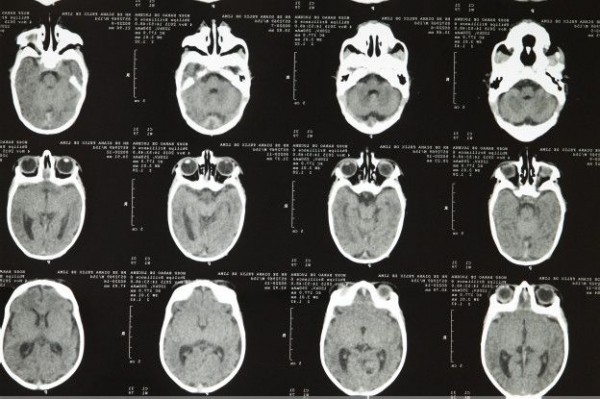

A partir de agora, exames pré-natal terão que ser feitos com mais atenção. Essa é a principal orientação, para os médicos responsáveis pelo acompanhamento das mulheres durante a gravidez. A preocupação surge com o aumento de casos de microcefalia em recém-nascidos detectados no Nordeste do País, supostamente causados pelo Zika vírus.

Os casos de bebês nascidos com microcefalia aumentaram mais de 400%, este ano, no Nordeste. O problema está atraindo a atenção de especialistas do Ministério da Saúde que investigam a relação entre as doenças.

Ministério da Saúde confirmou relação entre vírus zika e microcefalia.